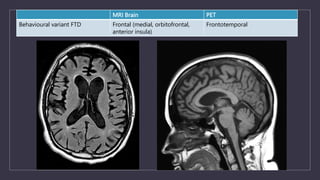

MRI Brain PET

Behavioural variant FTD Frontal (medial, orbitofrontal,

anterior insula)

Frontotemporal